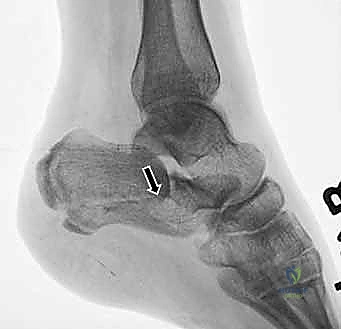

- التصوير بالأشعة السينية (X-rays): لأخذ فكرة أولية عن الكسر (زوايا بوهلر وجيسان - Bohler’s and Gissane’s angles).

- الأشعة المقطعية (CT Scan): وهي الخطوة الأهم والأكثر حيوية. توفر الأشعة المقطعية صوراً ثلاثية الأبعاد وتقاطعاً دقيقاً للكسر، مما يسمح بتصنيف الكسر (نظام ساندرز - Sanders Classification) وتحديد عدد الشظايا العظمية ومدى انزياحها داخل المفصل. بناءً على هذه الأشعة، يضع الدكتور هطيف خطته الجراحية الدقيقة.